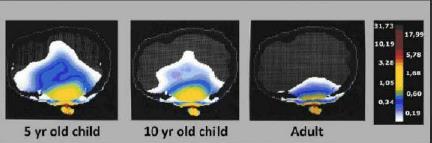

نرخ جذب ویژه (SAR) انرژی امواج ساتع شده از تلفن همراه در سر کودکان 3 تا 18 ماهه _ به منظور مقایسه با میزان جذب انرژی داخل بافت سر یک فرد بزرگسال در فرکانس مشخص

نرخ جذب ویژه (SAR) انرژی امواج ساتع شده از تلفن همراه در سر کودکان 3 تا 18 ماهه _ به منظور مقایسه با میزان جذب انرژی داخل بافت سر یک فرد بزرگسال در فرکانس مشخص

به گزارش خبرنگار حوزه دریچه فناوری گروه فضای مجازی باشگاه خبرنگاران جوان؛ در گزارش حوزه محافظت از کودکان در برابر امواج در پاسخ به چرایی آسیب پذیری آنها با استناد به تحقیقات علمی، گفته شده است که به دلیل سرعت رشد سیستم عصبی، ادامه بلوغ تا 20 سالگی، فعالتر بودن سلول های بنیادین در کودکان از عواملی هستند که آسب پذیری این قشر در برابر امواج را نسبت به بزرگسالان بیشتر می کند.

به گزارش خبرنگار حوزه دریچه فناوری گروه فضای مجازی باشگاه خبرنگاران جوان؛ در گزارش حوزه محافظت از کودکان در برابر امواج در پاسخ به چرایی آسیب پذیری آنها با استناد به تحقیقات علمی، گفته شده است که به دلیل سرعت رشد سیستم عصبی، ادامه بلوغ تا 20 سالگی، فعالتر بودن سلول های بنیادین در کودکان از عواملی هستند که آسب پذیری این قشر در برابر امواج را نسبت به بزرگسالان بیشتر می کند.